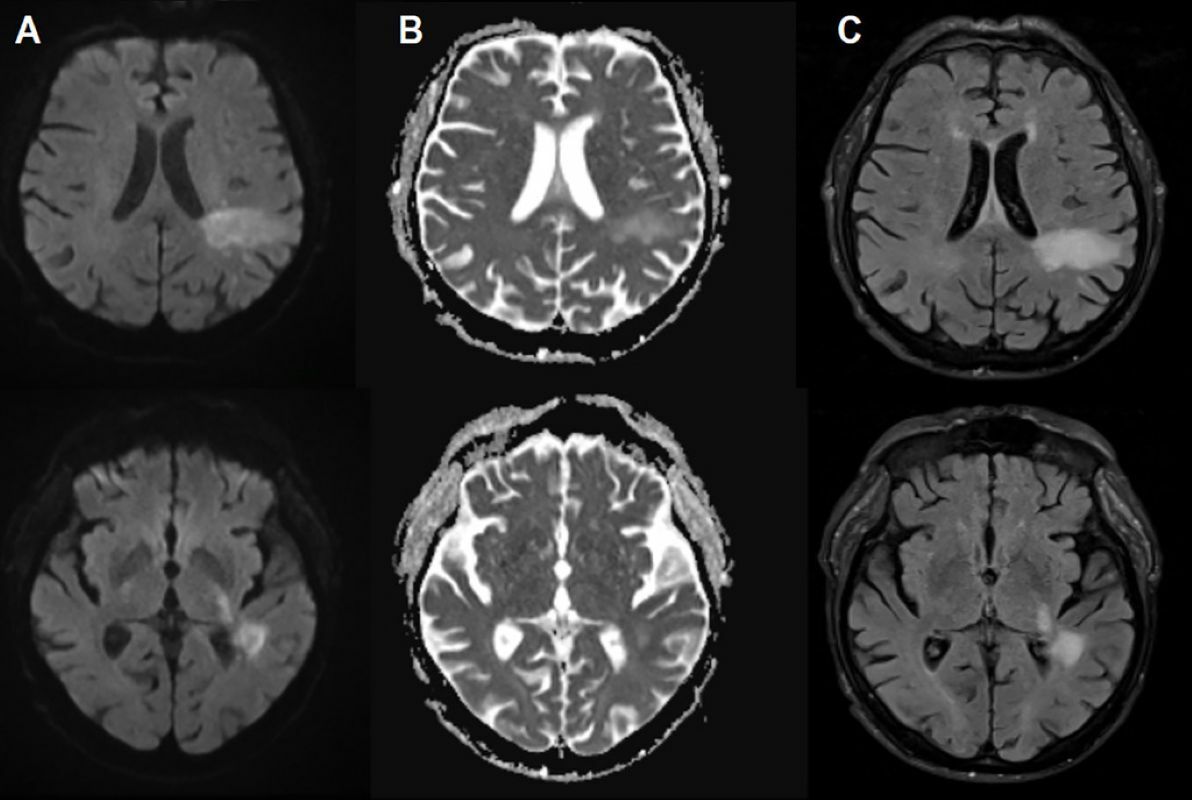

Magnetic resonance imaging of progressive multifocal leukoencephalopathy lesion

PML occurs when the virus undergoes a mutation to a more aggressive form which invades brain cells, destroying the protective myelin sheath around nerve fibers. This leads to severe neurological damage, with symptoms ranging from speech and vision problems to motor dysfunction and seizures. The disease was previously considered almost exclusively associated with profound immunosuppression, as in patients with HIV/AIDS or those undergoing strong immunosuppressive treatments.

The patient, who suffered from stage 5 kidney failure, was admitted with mental confusion, weakness and difficulty speaking. Initially, doctors suspected a condition related to the accumulation of toxins in the blood, common in severe cases of kidney disease. But when her symptoms worsened despite treatment, brain scans revealed lesions characteristic of PML. Later tests confirmed the presence of the JC virus in his central nervous system. The patient died just two days after diagnosis.